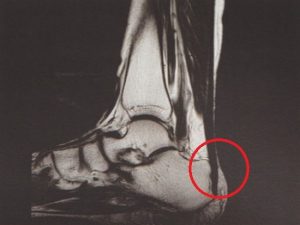

안양 고래한의원 - 아킬레스 건염001